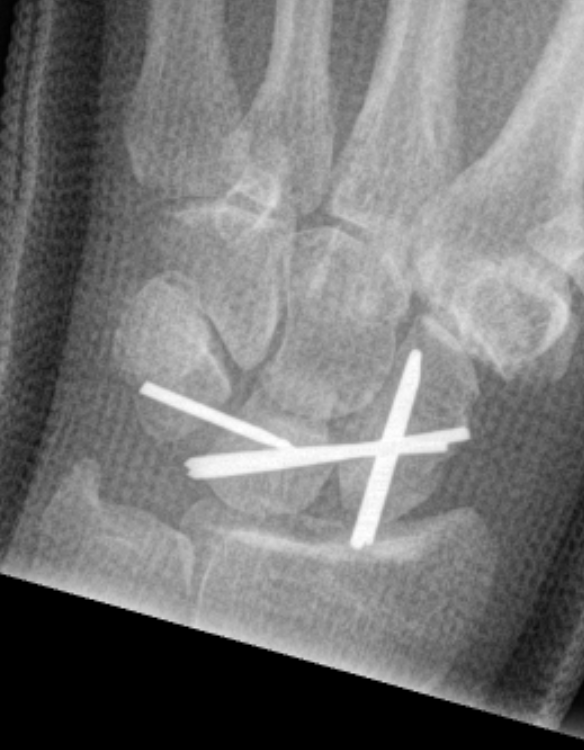

Perilunate dislocation / No scaphoid fracture

Technique

Dorsal approach

- 3/4 extensor compartment

- mobilise EPL laterally

- capsulotomy: T shaped or Berger (open dorsal between DRC and DIC ligaments)

- K wire joysticks in scaphoid and lunate and reduce

- K wires scaphocapitate / scapholunate / lunatetriquetral (areas of ligament rupture)

- +/- repair SL ligament if avulsed from scaphoid or lunate

- +/- repair LT ligament

- +/- reconstruction / internal brace SL and or LT ligament

- +/- SL screw

- +/- capsulodesis / tenodesis